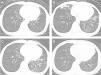

The patient is a 62-year-old, non-smoking, woman who was diagnosed with gastric cancer and was treated by total gastrectomy when she was 60. At the time of diagnosis of gastric cancer, chest computed tomography (CT) revealed mild bronchial wall thickening in both lower lobes (Fig. 1A). Six months after gastrectomy, follow-up chest CT showed consolidation in the right middle lobe and left lingular segment and consolidation, mucus plug, and centrilobular nodules in both lower lobes (Fig. 1B). Therefore, she was referred to the Department of Respiratory Medicine in Hikone Municipal Hospital.

Nineteen months after gastrectomy, follow-up chest CT showed improvement of the consolidation in the right middle lobe and left lingular segment, but there were no changes in the mucus plug and the centrilobular nodules in both lower lobes (Fig. 1C). There was also a persistent productive cough. Twenty-three months after gastrectomy, we initiated domiciliary nocturnal HFNC (myAIRVO™2, Fisher and Paykel Healthcare, Auckland, New Zealand) for humidification without oxygen at a flow rate of 30L/min and temperature of 34°C. Two months after the initiation of domiciliary nocturnal HFNC, the patient reported that the productive cough had reduced by half. Furthermore, repeat chest CT revealed decrease of mucus plug and centrilobular nodules (Fig. 1D). This patient did not have any of the adverse reactions induced by HFNC, such as pneumothorax, aerophagia, skin irritation, or epistaxis. During this clinical course, the patient had not undergone pulmonary rehabilitation.

In this patient, domiciliary humidification through HFNC was able to decrease the chest CT abnormalities (Fig. 1B–D) and the symptoms of productive cough. Rea et al.5 reported that domiciliary humidification through HFNC improved the lung function and quality of life of patients with chronic lower airway disorders, including chronic obstructive pulmonary disease and bronchiectasis. These effects of HFNC are considered to be caused by improvement in mucociliary clearance.6 Chronic aspiration after total gastrectomy is mainly induced by nocturnal esophageal reflux.4 This patient used HFNC only at night. Therefore, HFNC was considered to protect the patient from nocturnal aspiration, in addition to improving mucociliary clearance in this patient.